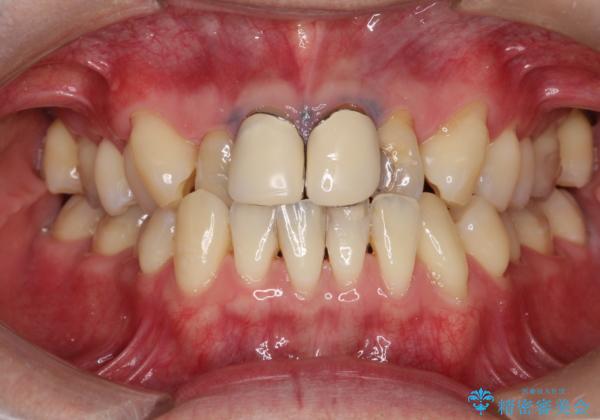

前歯とメタルタトゥー見た目が気になる 矯正・セラミックを組み合わせた治療

矯正治療で前歯の歯並びを整えてからセラミックほ装着する計画としました。

歯並びをかぶせ物のみで改善するのには限界があります。

矯正を併用することで、より審美的に良いかぶせ物を装着することが可能になります。